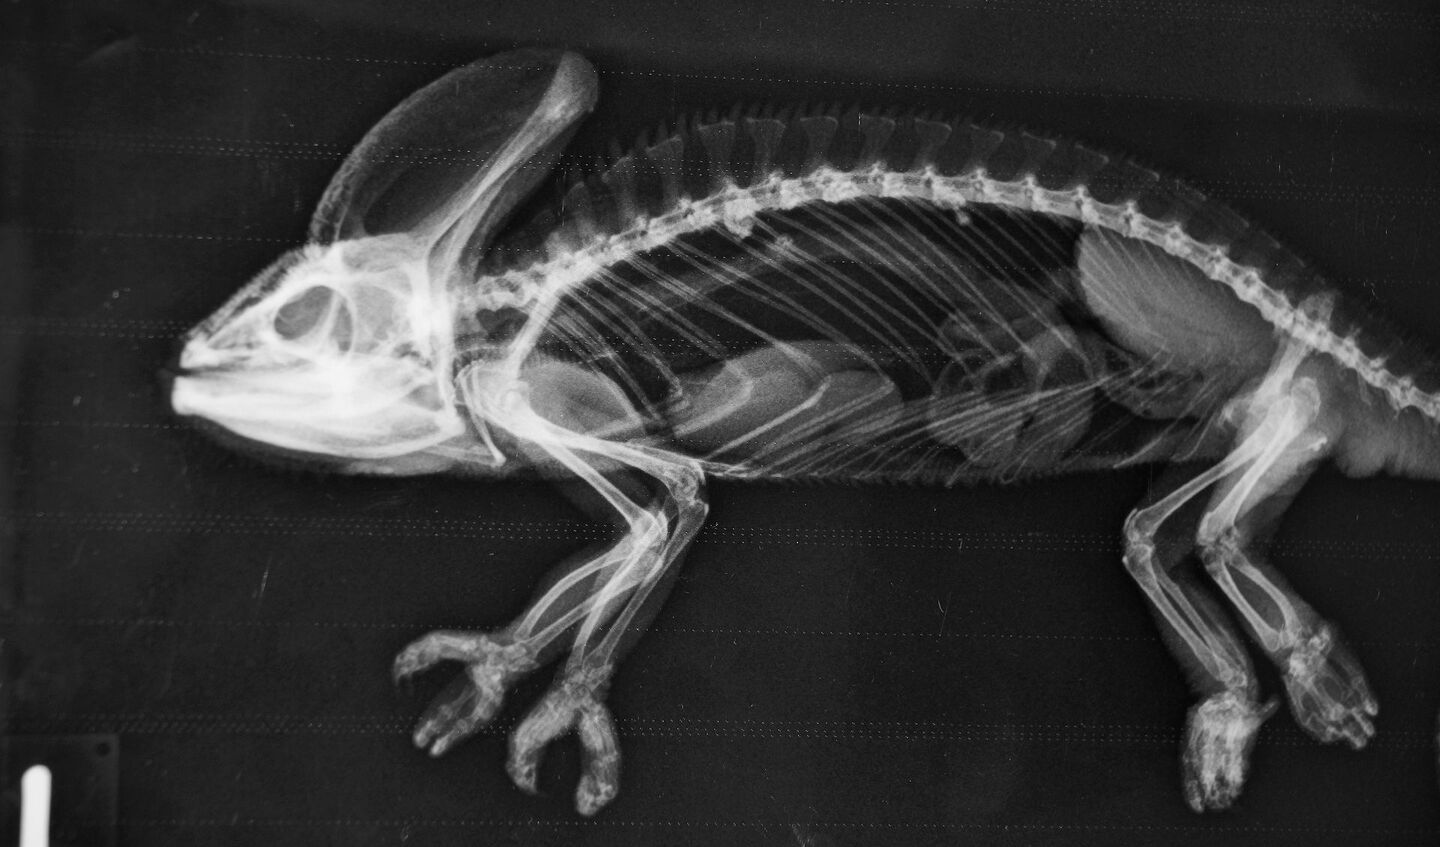

Einfacher auf dem Röntgentisch fixiert werden als ein Fisch kann eine Schildkröte. «Wir setzen sie auf eine Platte», sagt Christian Wenker. Bevor sie den Kopf aus dem Panzer schiebt, ist das Röntgenbild schon gemacht. Wie bei Vögeln kommt bei Reptilien Legenot vor, die mittels eines Röntgenbildes festgestellt werden kann. Damit Echsen wie Leguane nicht von der Röntgenplatte krabbeln, gibt es einen Trick. «Wir drücken kurz sanft und gleichzeitig auf die Augäpfel, dies führt über einen Vagusreflex zu einem betäubungsähnlichen Zustand», sagt der Zootierarzt.

[IMG 5]